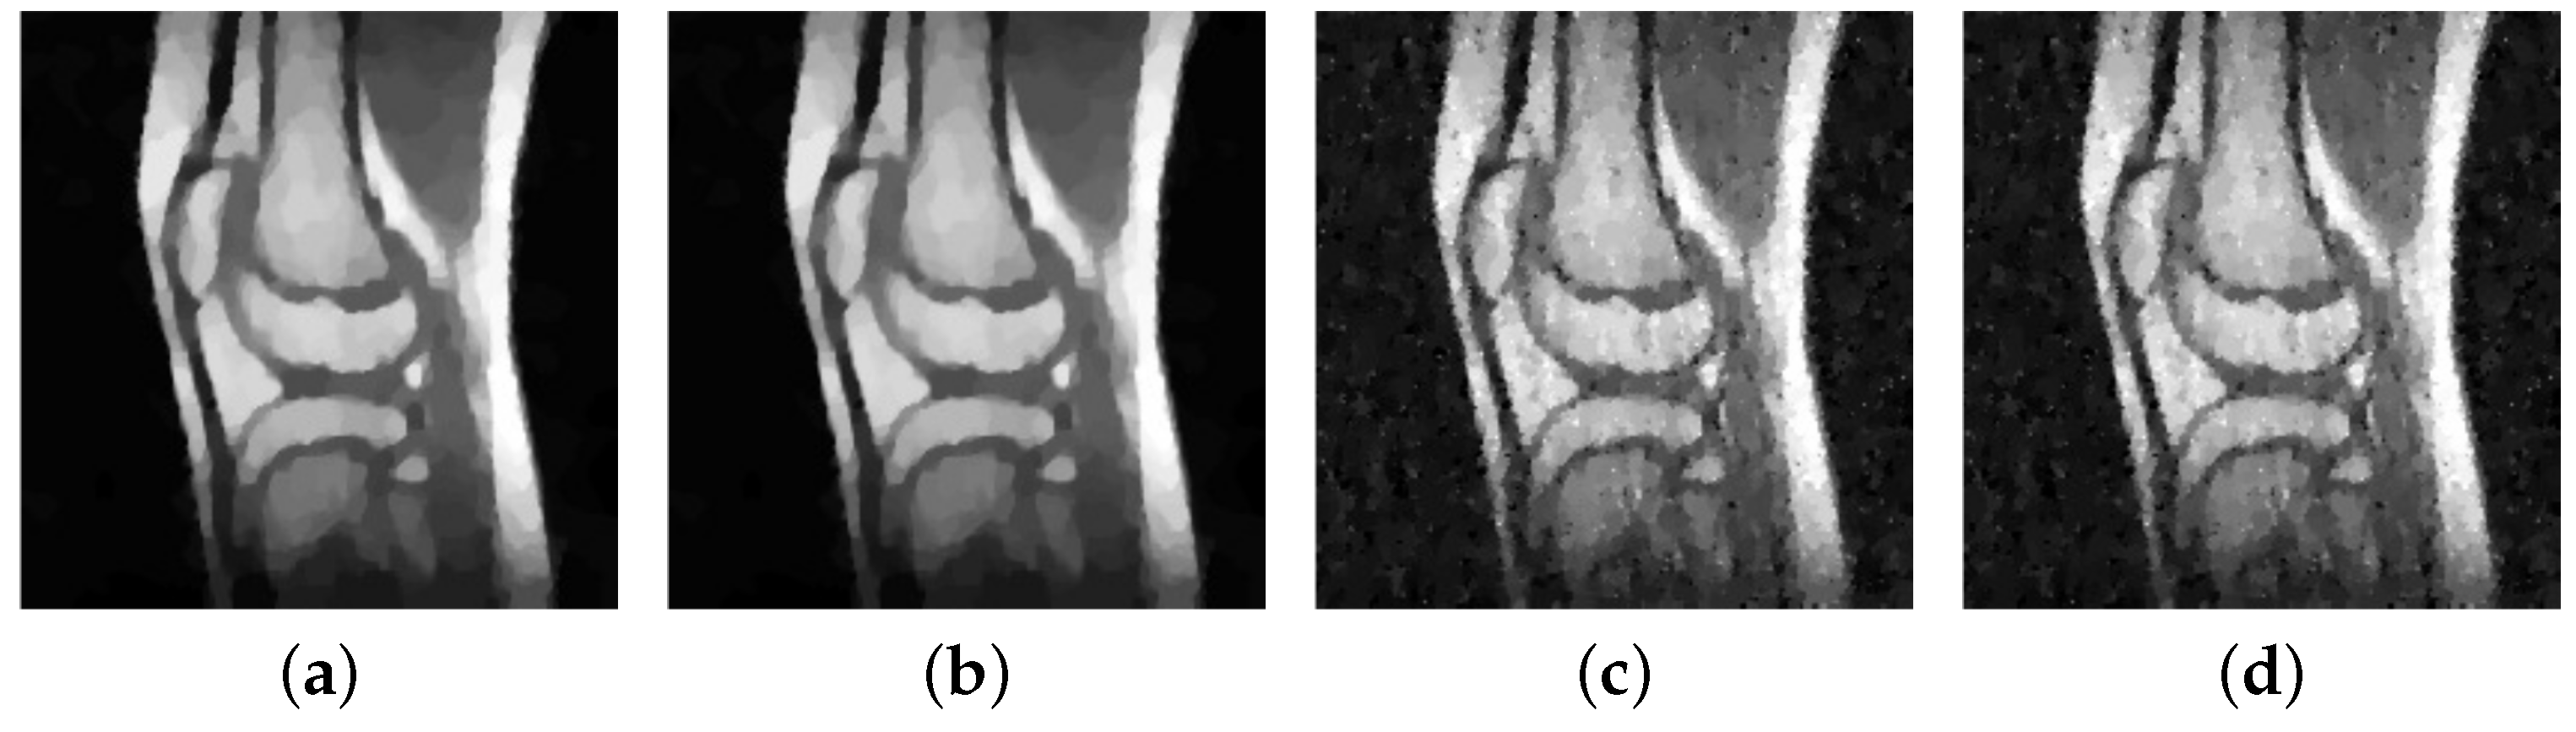

In our experiments we consider the images of Figure 2, transformed to its Fourier frequencies. As already mentioned, we sample the frequencies along 32 radial lines and add some Gaussian noise with zero mean and standard deviation . In particular, we consider different noise-levels, i.e., . We reconstruct the obtained data via the pAPS- and pLATV-algorithm by using the semi-smooth Newton method first with (no box-constraint) and then with (with box-constraint). In Table 13 we collect our findings. We observe that the pLATV-algorithm seems not to be suitable for this task, since it is generating inferior results. For scalar we observe as before, that a slight improvement with respect to PSNR and MSSIM is expectable when a box-constraint is used. In Figure 13 we present the reconstructions generated by the considered algorithms for a particular example, demonstrating the visual behavior of the methods.

Figure 13.

Reconstruction from sampled Fourier data. (a) pAPS with pdN with (PSNR: 25.017; MSSIM: 0.37061); (b) pAPS with box-constrained pdN (PSNR: 25.017; MSSIM: 0.37056); (c) pLATV with box-constrained pdN (PSNR: 23.64; MSSIM: 0.34945); (d) pLATV with pdN with (PSNR: 23.525; MSSIM: 0.34652).